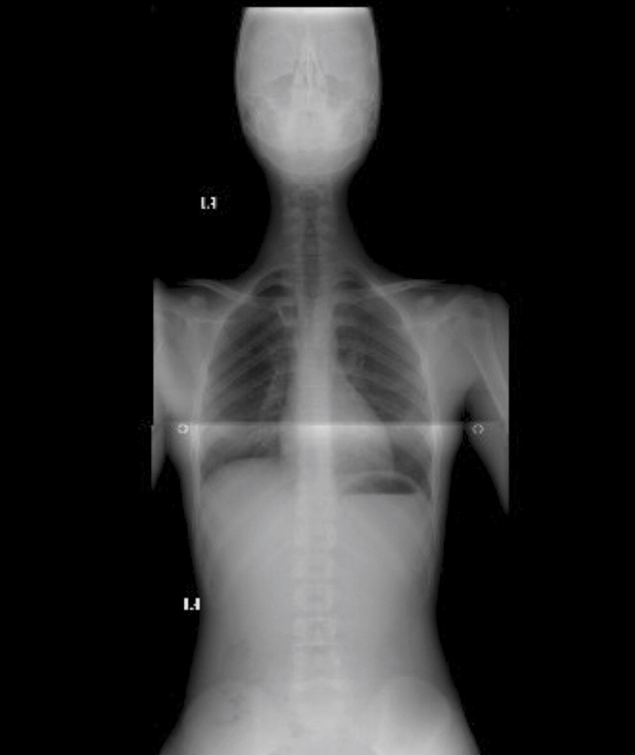

Egzersizlere ilk başladığımda, merkeze haftanın 3 günü geliyordum. Elif Hanım, daha iyi sonuç almamız için böyle bir program oluşturmuştu. Daha sonra haftada iki kez birer saat egzersiz yapmaya başladık ve bir yılın sonundan adeta bir mucize oldu. Artık ağrılarımdan neredeyse tamamen kurtulmuştum. Kontrol için doktora gittiğimde, skolyozumun ölçülemeyecek kadar gerilediğini söyledi.

Artık kambur oturmuyorum. Duruşum, postürüm düzeldi. Geceleri çok rahat uyuyorum, sabah daha iyi uyanıyorum. Ağrılarımdan kurtulunca çok sevdiğim basketbola da geri döndüm, artık daha iyi oynuyorum.

Doktorum, egzersizlere devam edip etmeme kararını bana bıraktı. Elif Hanım ile yaptığımız görüşme neticesinde, basketbol da oynadığım için egzersizlere haftada bir gün devam etme kararı aldık. Böylece ben hem daha güçlü bir omurgaya sahip olacağım hem de vücudum daha esnek olacak. Keza skolyozun tekrar etmemesi için de önlem almış olacağım.”